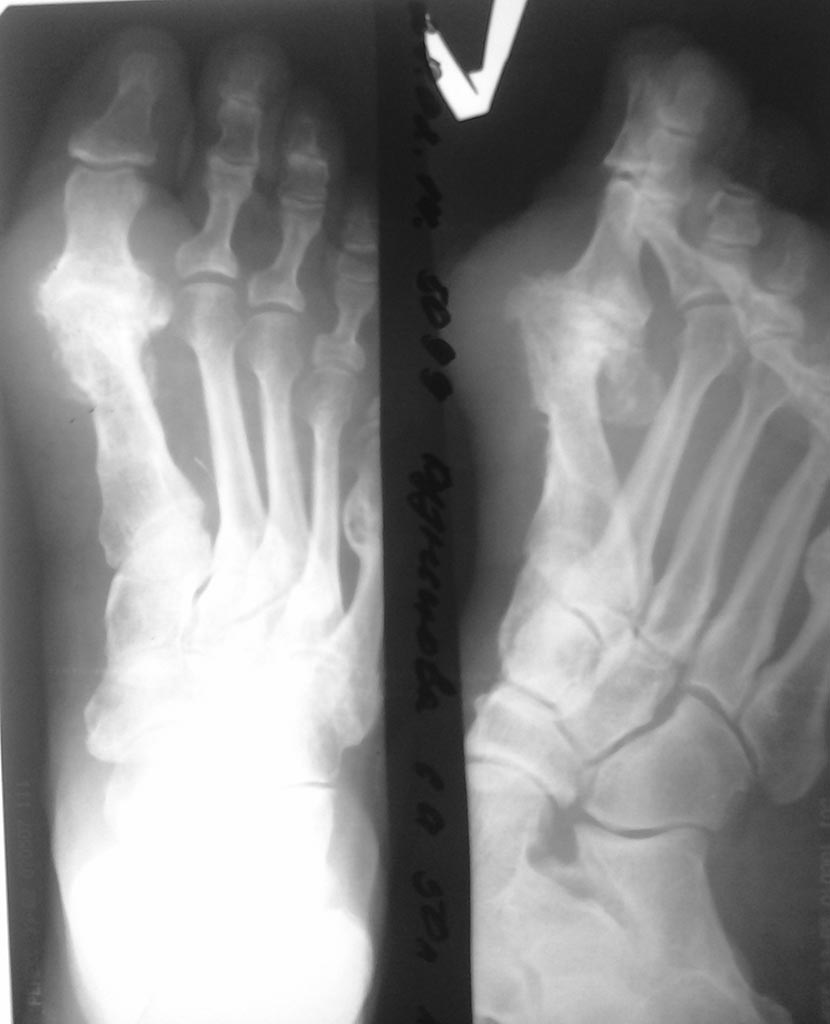

Доброе время суток, помогите пожалуйста с тактикой лечения. Пациентке 50 лет в анамнезе корректирующая операция на костях 1 луча левой стопы, в настоящее время беспокоят боли в проекции 1 луча при опоре на стопу.

Рентгенологически и клинически артродез 1 плюсне-фалангового сустава состоялся. Что-бы Вы порекомендовали в плане лечения.

Такие массивные разрастания вокруг сустава скорее говорят о том, что костный анкилоз не состоялся. Вероятно, имеется фиброзный анкилоз. Это облегчает задачу. Нужно убрать костные разрастания вокруг сустава и выполнить артродез, правильно установив суставные поверхности.Ну и конечно всю картину по представленным снимкам оценить сложно. Например, что там за выпуклость на 5 плюсневой кости?

Добрый день, уважаемые коллеги. А почему вы решили, что предыдущие хирурги стремились к артродезу первого плюснефалангового сустава? По моему речь идет о исходе одного из вариантов остетотомии первой плюсневой кости, которыцй закончился асептическим некрозом головки 1 плюсневой кости. И сейчас вы имеете ситуацию, обозначасемую, как hallux rigidus. И думать надо о возможной мобилизации первого плюснефалангового сустава.